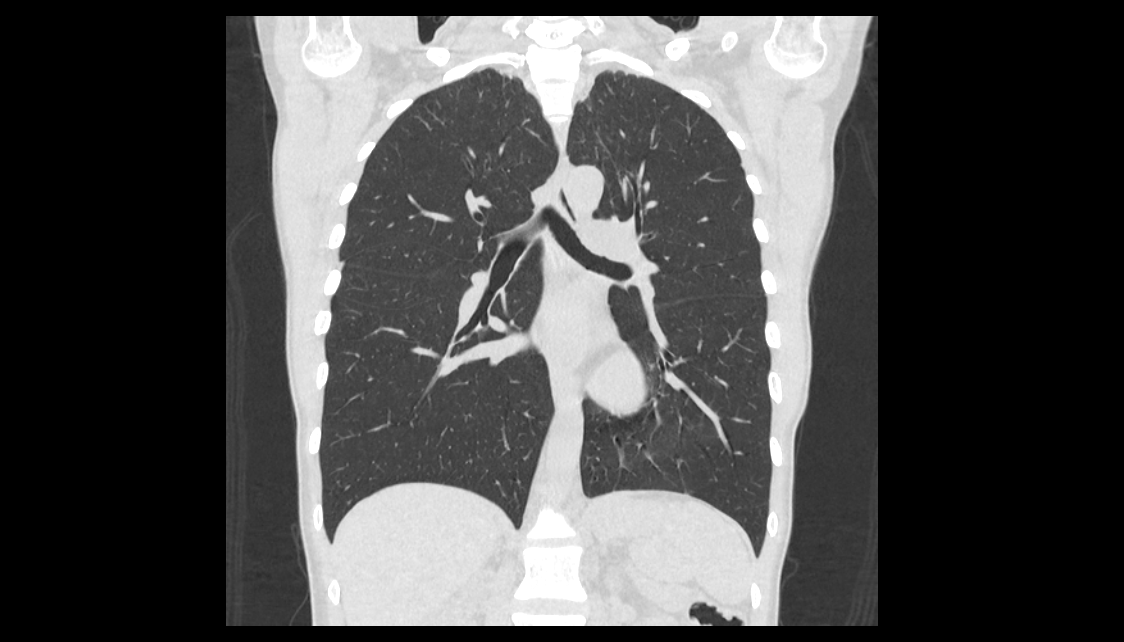

Во время исследования рентгеновская трубка томографа вращается вокруг исследуемой области и производит множество послойных снимков с шагом 0,5-1 мм. Полученные снимки поперечного сечения с помощью компьютерной программы могут быть преобразованы в 3D-изображения исследуемого органа или участка ткани. Это позволяет выявлять практически все заболевания легких на ранних стадиях и назначать своевременное лечение.

В медицинском центре «Доступная медицина» используется современный 128-срезовый компьютерный томограф TOSHIBA AQUILION CXL, на котором проводится сканирование легочной ткани. За счет увеличенного количества детекторов аппарат производит снимки с большой скоростью и минимальной дозой облучения. При этом инновационные цифровые приложения позволяют получить объемные изображения легочной ткани высокой четкости, контрастности и в мельчайших подробностях.

При проведении мультиспиральной КТ легких можно диагностировать различные заболевания, в том числе: